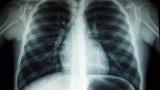

Самые распространённые «виновники» пневмонии — пневмококки, стрептококки, гемофильная палочка, легионелла и др. Но бывают и атипичные возбудители. Недавние вспышки заболевания вызывала бактерия микоплазма. Инфекция передаётся воздушно-капельным путём и поражает лёгкие необычным способом.

Местом своего обитания в организме микоплазма выбирает стенки бронхов, может прикрепиться к стенкам альвеол в так называемой промежуточной ткани лёгких. Соответственно, поражает она не саму ткань этих парных органов, а их сосуды и соединительные ткани, поэтому первые 7−12 дней болезнь протекает тихо, без хрипов. Но, если не начать лечиться, появится сухой изнурительный кашель. Так что заподозрить заболевание непросто.

Обычно микоплазменные пневмонии протекают легче, чем пневмококковые, если лечение подоспеет вовремя. При подозрении на атипичную пневмонию, как и при ковиде, требуется проведение КТ лёгких. «Тихая пневмония» лечится антибиотиками, но не теми, что помогают от пневмококков. Конкретное лекарство порекомендует доктор. Но, если затянуть с обращением к врачу, могут развиться тяжёлые осложнения со стороны дыхательной, нервной и сердечно-сосудистой систем, присоединиться более серьёзная инфекция.